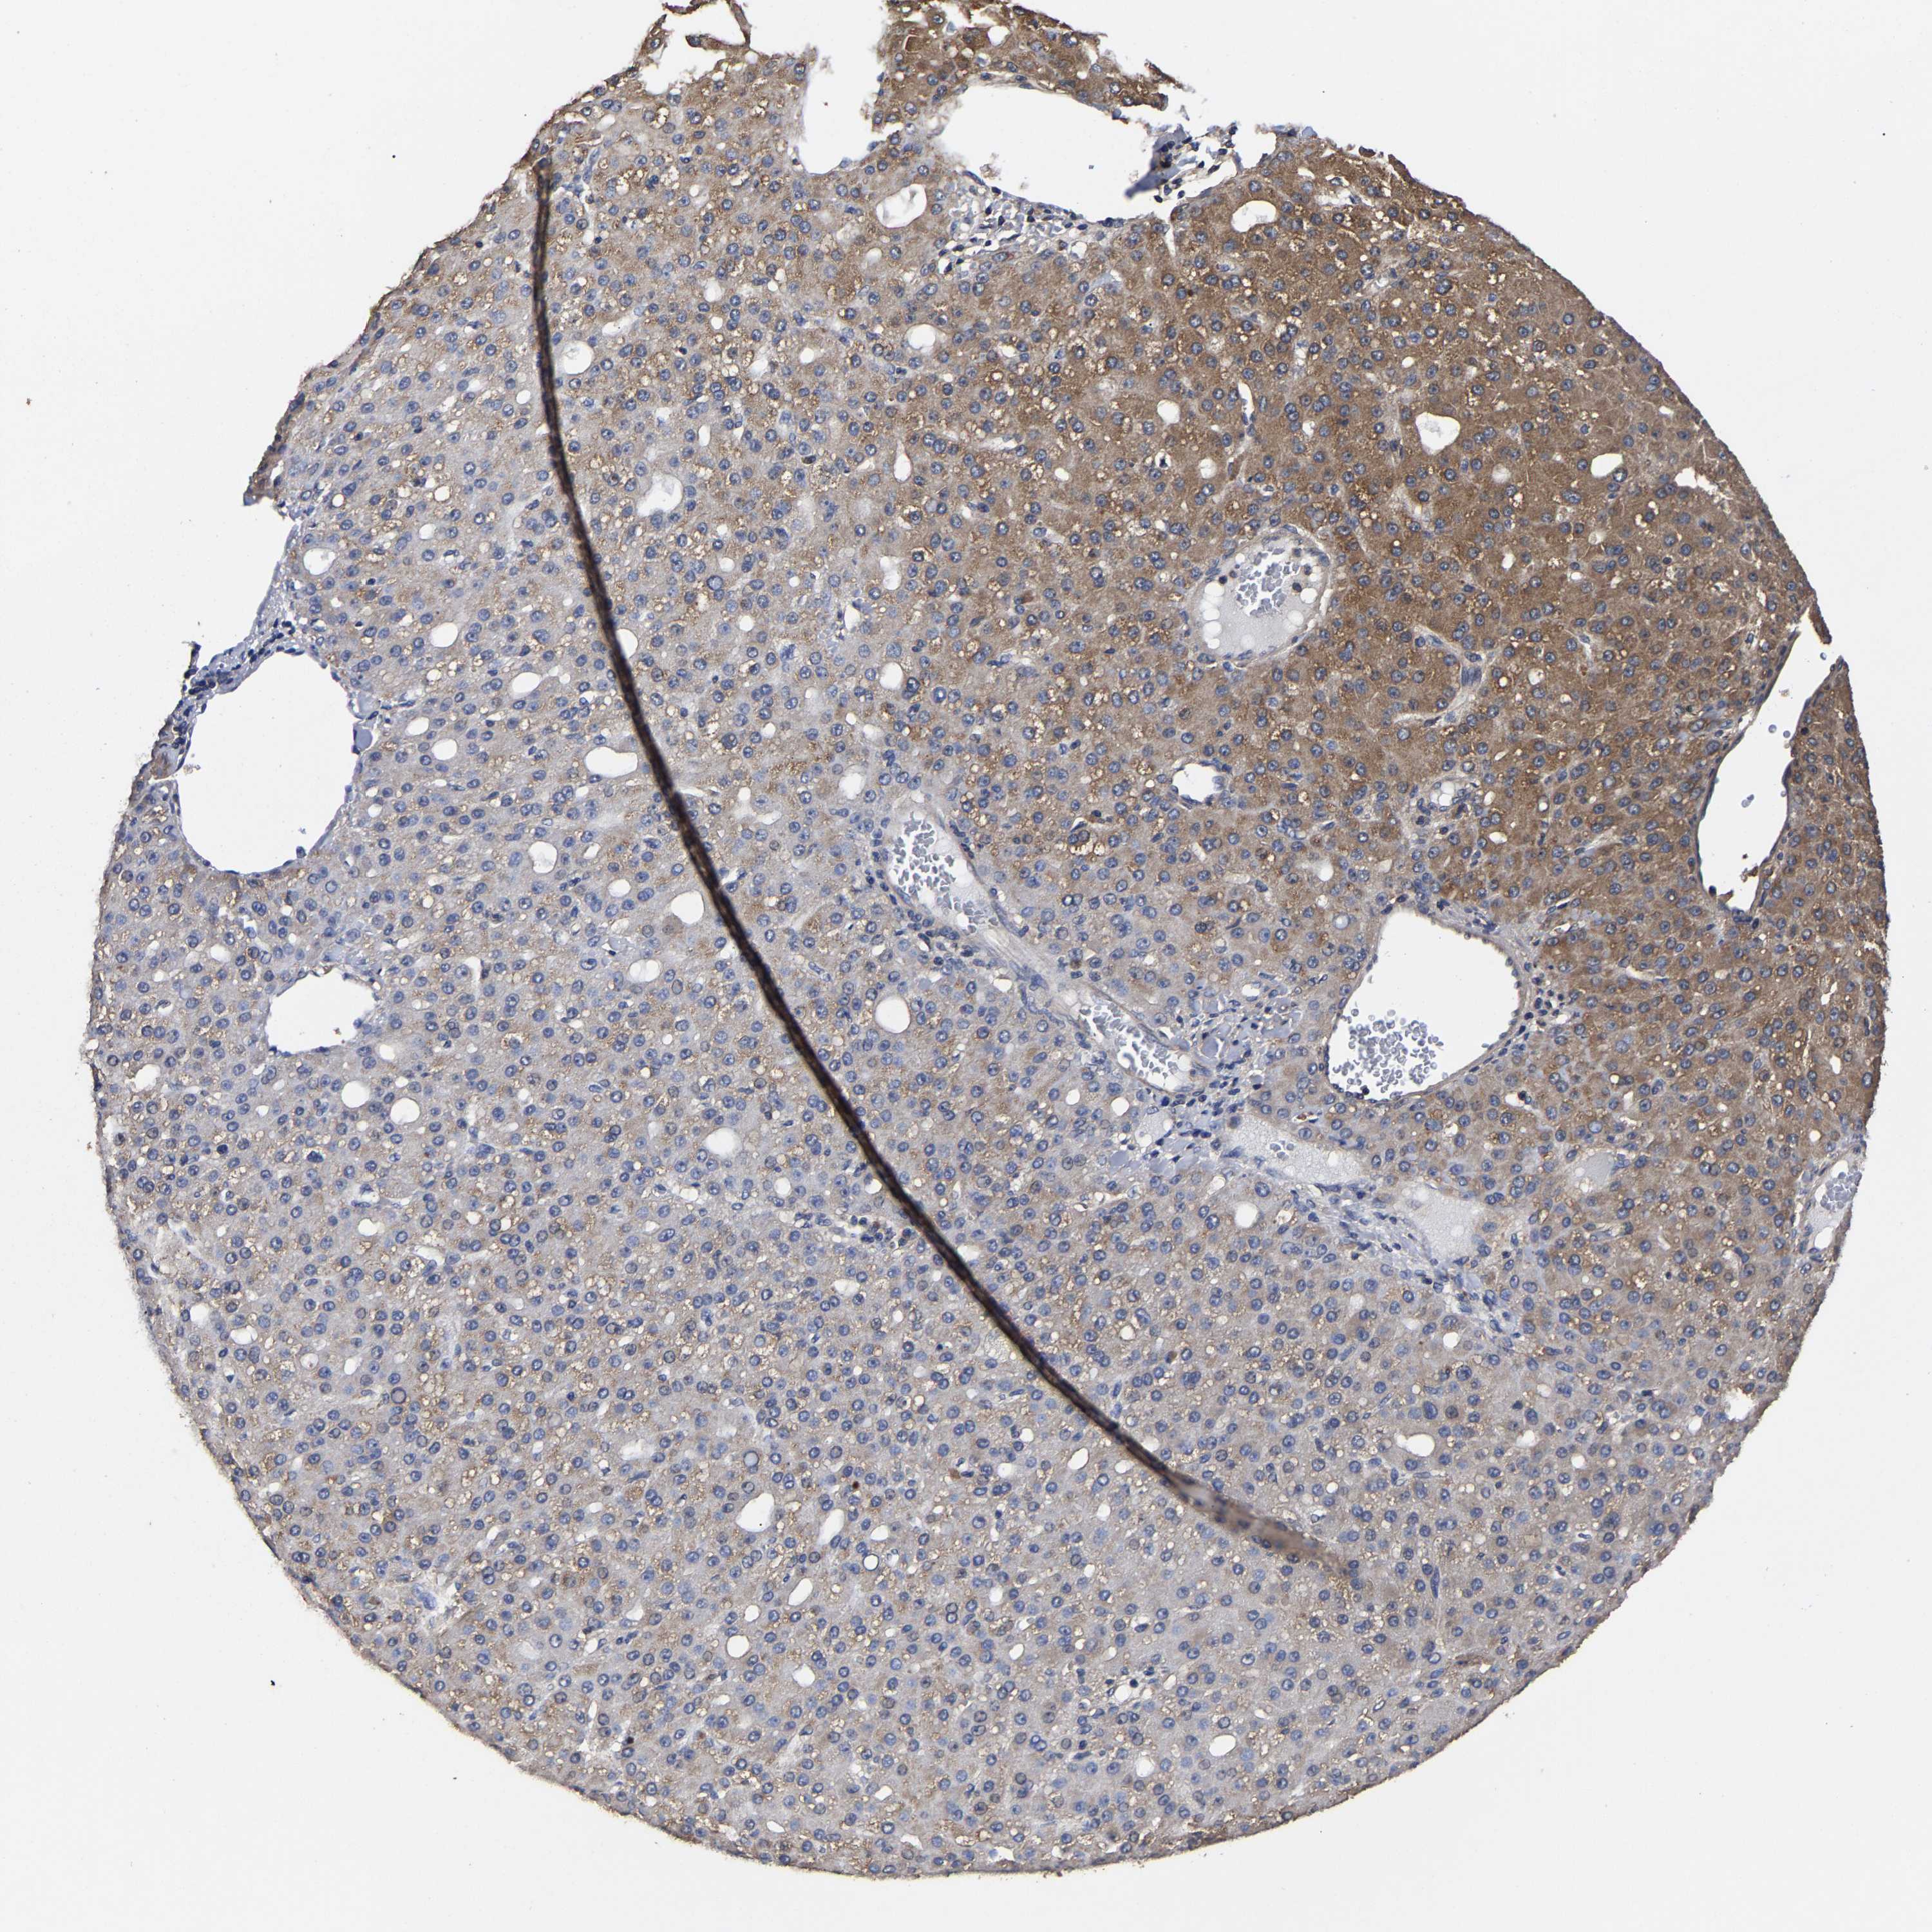

LIVER CANCER